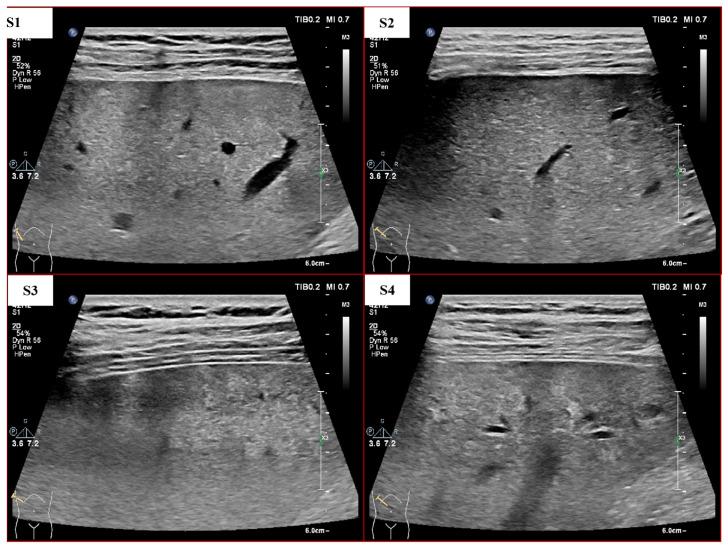

Due to the heterogeneity of ultrasound (US) images and the indeterminate US texture of liver fibrosis (LF), automatic evaluation of LF based on US images is still challenging. Thus, this study aimed to propose a hierarchical Siamese network that combines the information from liver and spleen US images to improve the accuracy of LF grading. There were two stages in the proposed method. In stage one, a dual-channel Siamese network was trained to extract features from paired liver and spleen patches that were cropped from US images to avoid vascular interferences. Subsequently, the L1 distance was used to quantify the liver-spleen differences (LSDs). In stage two, the pretrained weights from stage one were transferred into the Siamese feature extractor of the LF staging model, and a classifier was trained using the fusion of the liver and LSD features for LF staging. This study was retrospectively conducted on US images of 286 patients with histologically proven liver fibrosis stages. Our method achieved a precision and sensitivity of 93.92% and 91.65%, respectively, for cirrhosis (S4) diagnosis, which is about 8% higher than that of the baseline model. The accuracy of the advanced fibrosis (≥S3) diagnosis and the multi-staging of fibrosis (≤S2 vs. S3 vs. S4) both improved about 5% to reach 90.40% and 83.93%, respectively. This study proposed a novel method that combined hepatic and splenic US images and improved the accuracy of LF staging, which indicates the great potential of liver-spleen texture comparison in noninvasive assessment of LF based on US images.

由于超声(US)图像的异质性和肝纤维化(LF)的不确定 US 纹理,基于 US 图像的 LF 自动评估仍然具有挑战性。因此,本研究旨在提出一种层次暹罗网络,该网络结合了来自肝和脾 US 图像的信息,以提高 LF 分级的准确性。该方法有两个阶段。在第一阶段,训练了一个双通道暹罗网络,从从 US 图像中裁剪出的配对肝和脾补丁中提取特征,以避免血管干扰。随后,使用 L1 距离量化肝脾差异(LSD)。在第二阶段,将第一阶段的预训练权重转移到 LF 分期模型的暹罗特征提取器中,并使用肝和 LSD 特征的融合训练分类器进行 LF 分期。这项研究是对 286 名经组织学证实的肝纤维化分期患者的 US 图像进行的回顾性研究。我们的方法在肝硬化(S4)诊断方面的精度和灵敏度分别达到 93.92%和 91.65%,比基线模型高约 8%。先进纤维化(≥S3)诊断和纤维化多分期(≤S2 与 S3 与 S4)的准确性均提高了约 5%,分别达到 90.40%和 83.93%。本研究提出了一种新的方法,该方法结合了肝和脾 US 图像,并提高了 LF 分期的准确性,这表明在基于 US 图像的 LF 无创评估中,肝脾纹理比较具有很大的潜力。